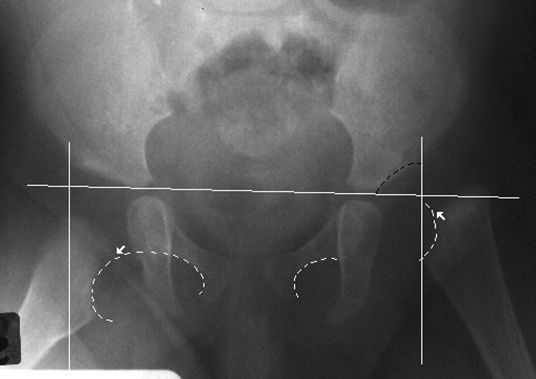

正常骨盆正位片

常见髋关节测定线